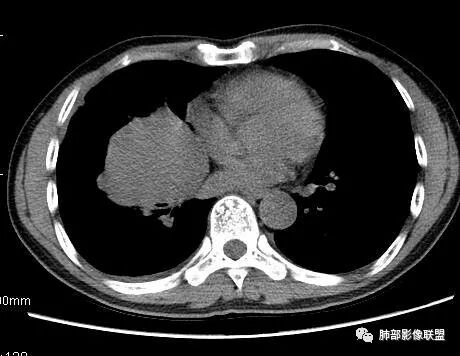

南边:深分叶、大肿块

南边:主体在下叶前基底段

南边:边缘膨隆

南边:中叶、下叶背段支气管推移

南边:中叶支气管腔内似有粘液栓,外侧段有炎性病变

南边:病灶边界清,提示侵袭性弱,膨胀生长为主;这时候我们提示病灶不应该是支气管关系密切,提示间叶来源或胸膜来源

深分叶,警惕恶性

常规考虑:1、肉瘤首先考虑

2、胸膜孤立性纤维瘤待排

南边:结果:肉瘤